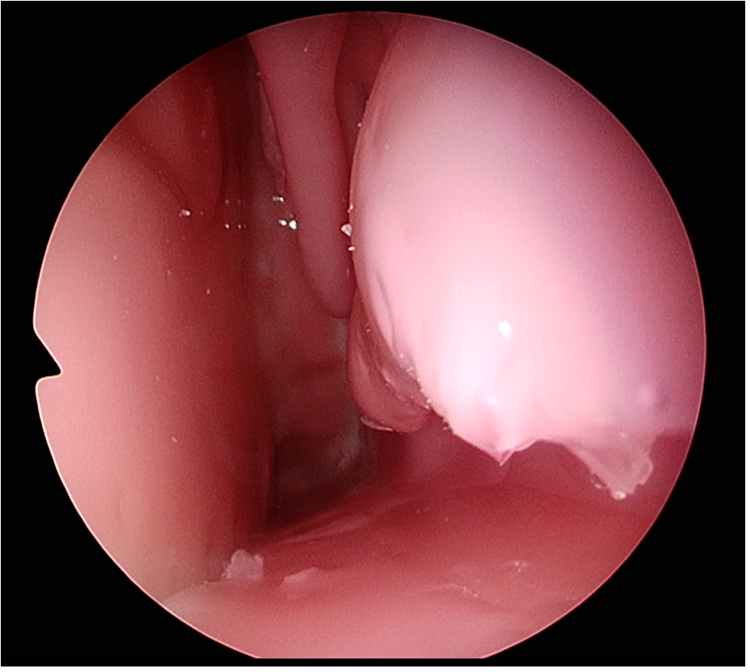

Step (1) on the TNS Box is demonstrated in

Figure 3and anterior sphenoidotomy in

Figure 4.

Figure 3

Participant identifying choana and nasal turbinate's on the TNS Box.